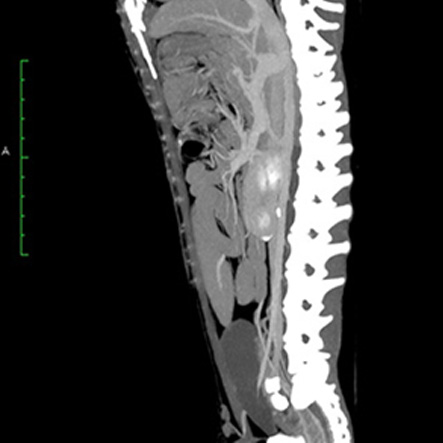

CT検査により、通常の画像検査では検出しにくい病気の早期発見・診断につながる可能性が高まります。

CT画像の検査・読影のみも受け付けております。